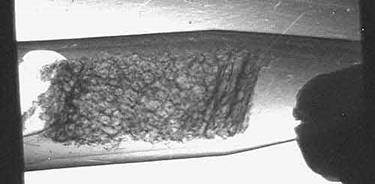

На Курчатовском источнике СИ были проведены исследования биоптатов костной ткани человека, предоставленные Центральным институтом травматологии и ортопедии им.Н.Н.Приорова (ЦИТО). Биоптаты представляют собой небольшие фрагменты, объемом менее одного кубического сантиметра, извлеченные посредством операции из кости и помещенные в формалин. На рис.5 показаны снимки, сделанные методом рефракции (а) и поглощения (б). Видно, что структура кости на рис.5,а проявляется значительно лучше, чем на рисунке 5,б. На верхнем рисунке хорошо виден внешний (кортикальный слой) кости, а также внутренний, который состоит из продольных слоев (трабекул) размером до нескольких сотен микрон. Здесь использование синхротронного излучения приобретает особое значение, потому что другие методы для оценки прочности кости оказываются малоприменимыми. Хотя с помощью электронного микроскопа, дающего очень высокое пространственное разрешение, можно увидеть в кости кристаллы кальцита размером около 1 мкм, но в практической медицине это пока не нашло широкого применения. На синхротронных пучках размеры и ориентацию таких кристаллов удается определять с помощью электронной спектроскопии.

Рис. 5. Изображение биоптата кости человека, полученное методом рефракции (а) и поглощения (б) на Курчатовском источнике СИ.